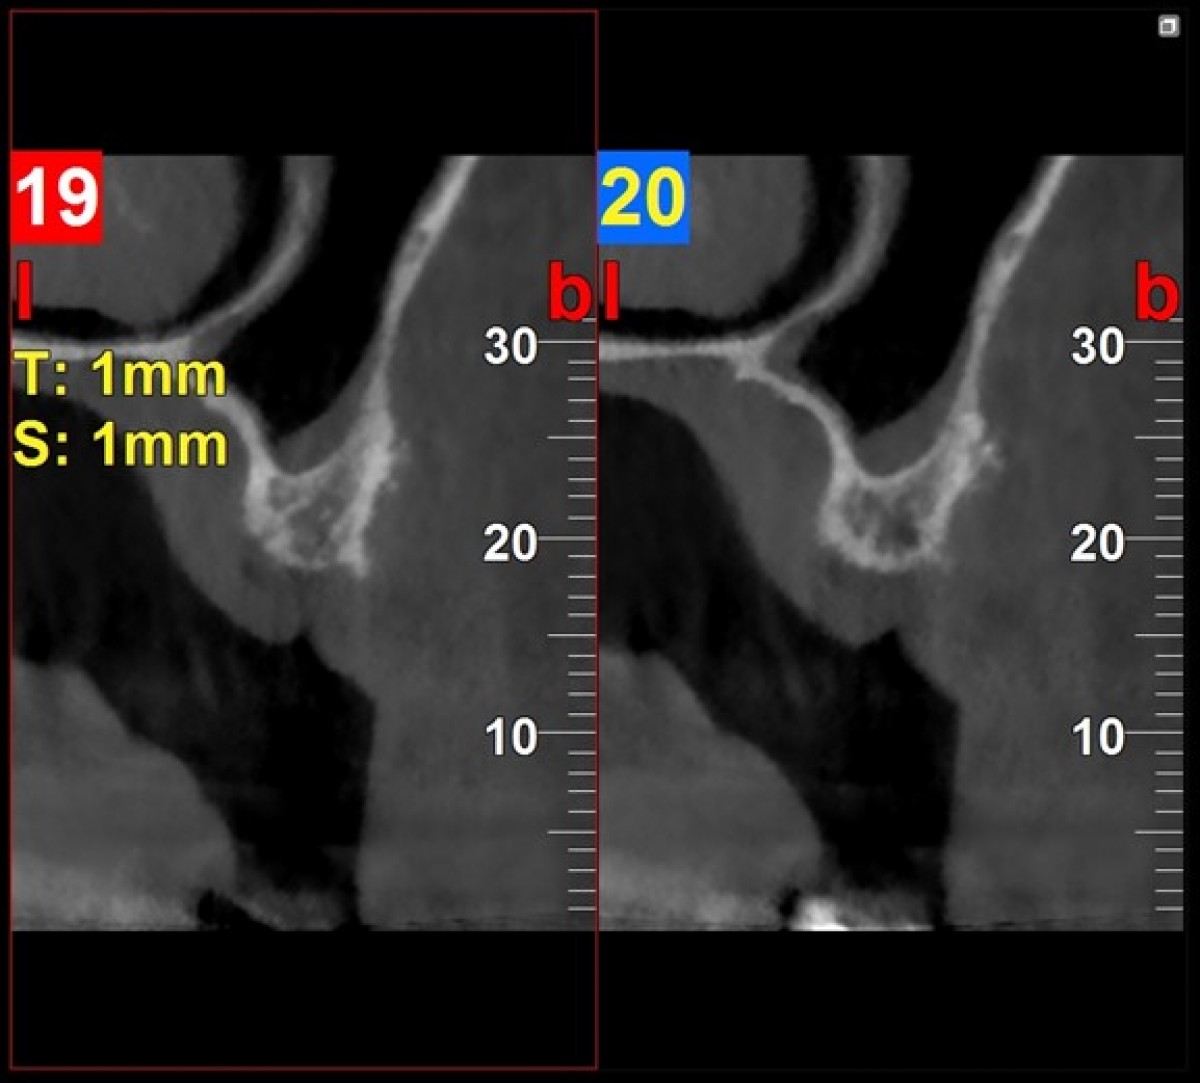

The two-dimensional control X-ray performed at the end of the healing period demonstrates sufficient bone to accommodate the implant fixtures. However, the complexity of the case, the proximity of the maxillary sinus, and the need for a more precise assessment of bone volumes justified the execution of a CBCT with FOV 4x4 and a "Regular"

The tomographic cuts obtained (Fig. 6 and Fig. 7) allowed the accurate evaluation of the residual bone volumes and the adjacent anatomical structures not otherwise appreciable in the two-dimensional view of the site, allowing the operator to insert the implants in complete safety and full compliance of the patient's anatomy (Fig. 8)